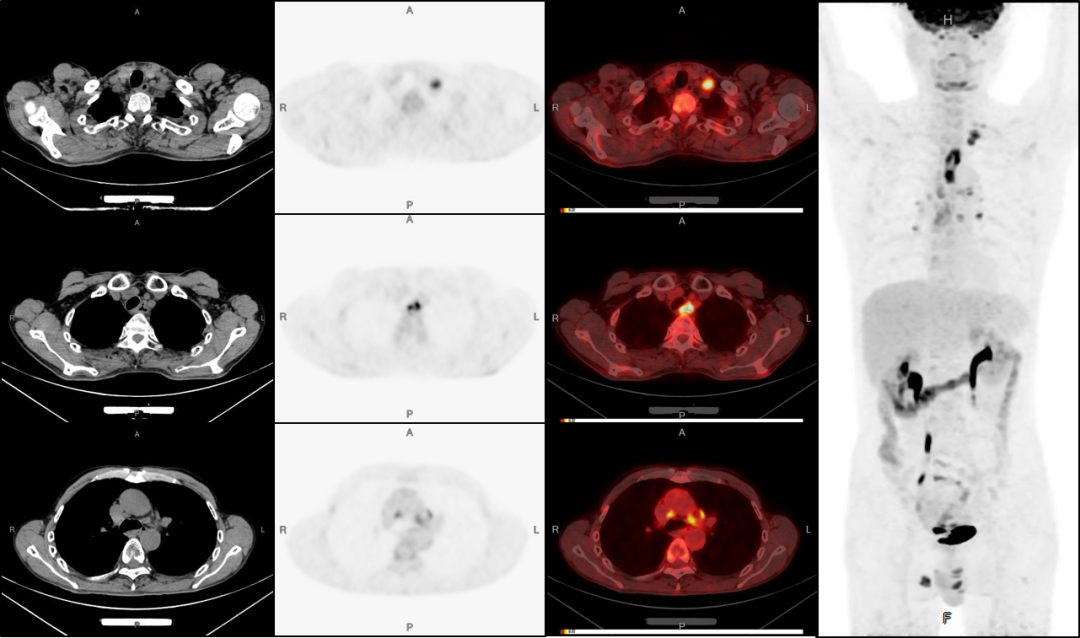

病例3:男性,72歲。結(jié)腸腺癌術(shù)后3年,右肺鱗癌術(shù)后1年隨訪。

PET/CT檢查:

1、全身多發(fā)骨轉(zhuǎn)移;

2、右側(cè)鎖骨區(qū)、縱膈及左側(cè)肺門多發(fā)淋巴結(jié)轉(zhuǎn)移;

3、腹膜后淋巴結(jié)轉(zhuǎn)移待排;

4、肝脾多發(fā)轉(zhuǎn)移灶可能。